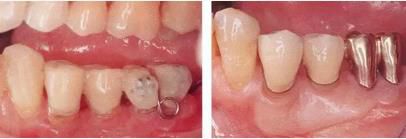

360截圖20170422101744009.jpg

▲圖5-1,2

▲圖5-1 左下5舌側(cè)移位,頰系帶高位附著,附著齦不足,口腔前庭狹小,左下6根分叉病變,左下7擴(kuò)散性骨組織吸收深達(dá)根尖部等,存在非常多的問(wèn)題。

▲圖5-2 確認(rèn)左下7骨組織吸收深達(dá)根尖部,初期治療時(shí)拔除。將左下7拔除后的X光片。